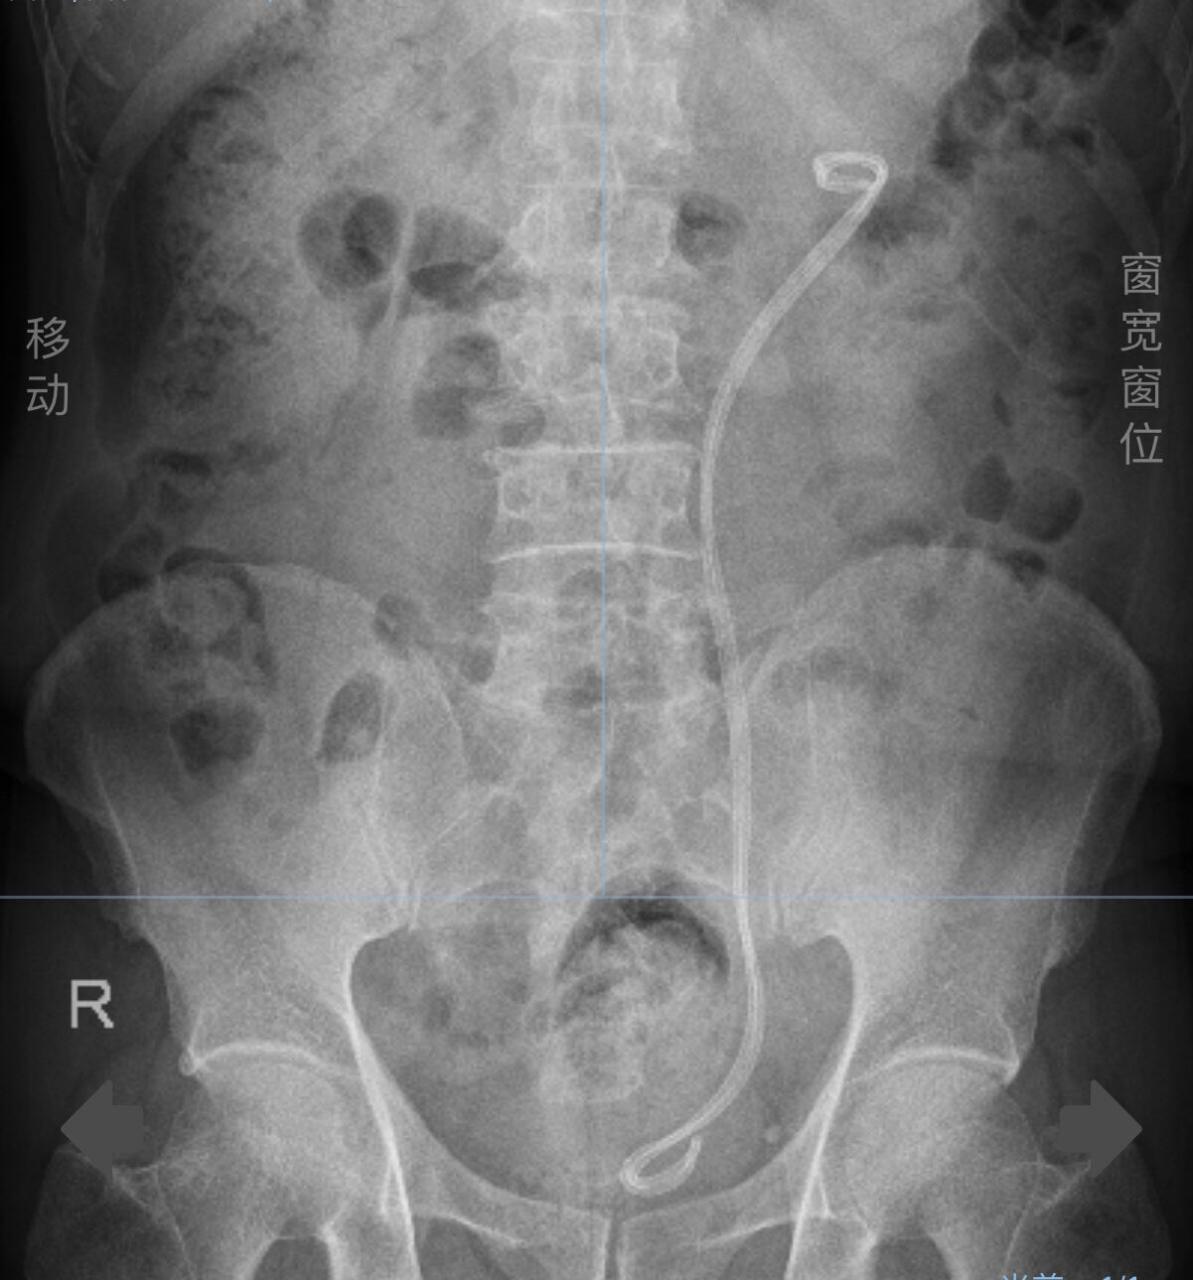

留置双j管后腹部正位x光片dj管的主体放置于输尿管内,两端分别位于

输尿管放置双j管图片